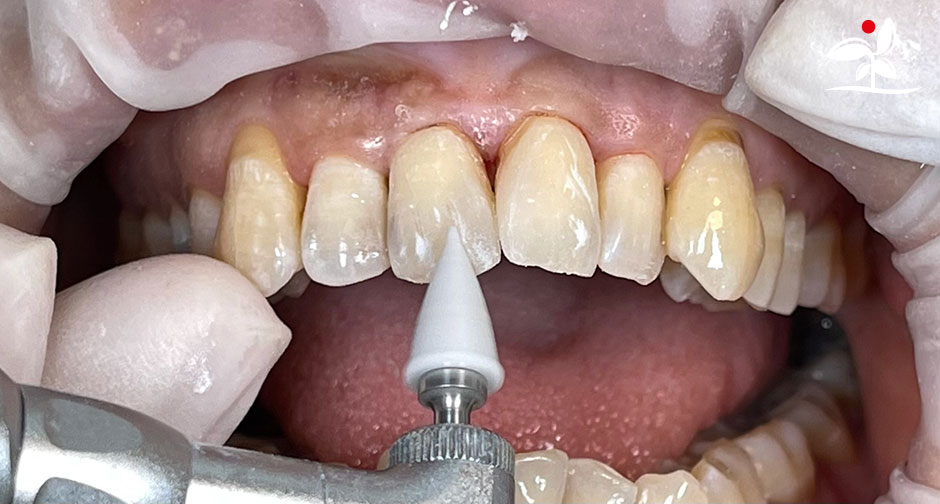

Restoration of Class IV Lesions using Naturomimetic Layering Technique (NLT) and Bioactive Restorative Materials

With the growing awareness about the health, function and aesthetic benefits of preserving natural tooth structure, patients are now globally demanding for aesthetic dentistry with minimally invasive procedures that has a low biological cost. This public demand has encouraged logical clinicians to adopt to the minimally invasive cosmetic dentistry (MiCD) concept and its treatment protocol [1] in their practice. The author has been using MiCD concept and its treatment protocols since 2017, which

include the methods of treatment that are simple, fast, predictable and healthy. In aesthetic restoration, the tooth color restorative materials placement technique is one of the most challenging, confusing and frustrating areas to learn owing to the multiple techniques that have been proposed by many clinicians and replicating such techniques in practice is not always as easy as they are marketed in dentistry. Natural teeth are complex in structure and hard to simulate due distribution of colors through enamel and dentin [2]. Aesthetic restoration strategies should follow proper understanding of defects, right selection of restorative materials along with their proper application, finishing, texturing and polishing [2].